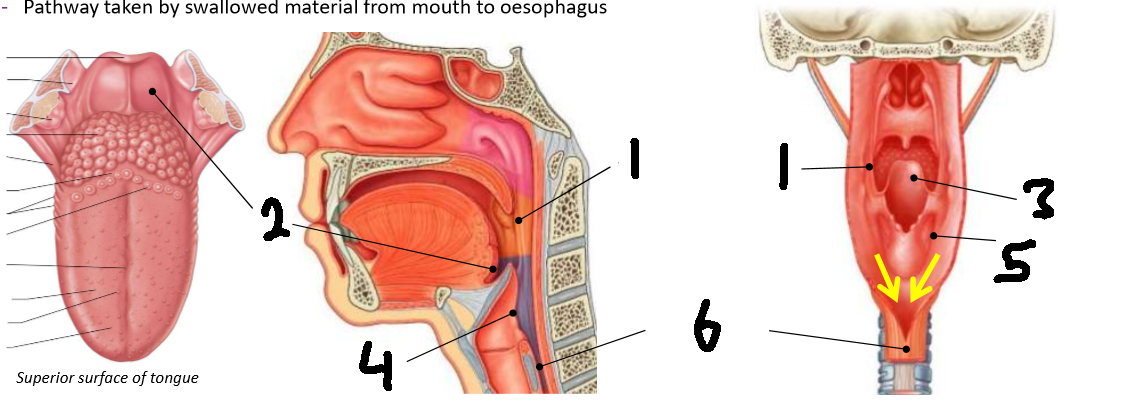

What is 1?

palatopharyngeal arch

What is 2?

vallecula

What is 3?

epiglottis

What is 4?

laryngeal inlet

What is 5?

piriform fossa

What is 6?

oesophagus